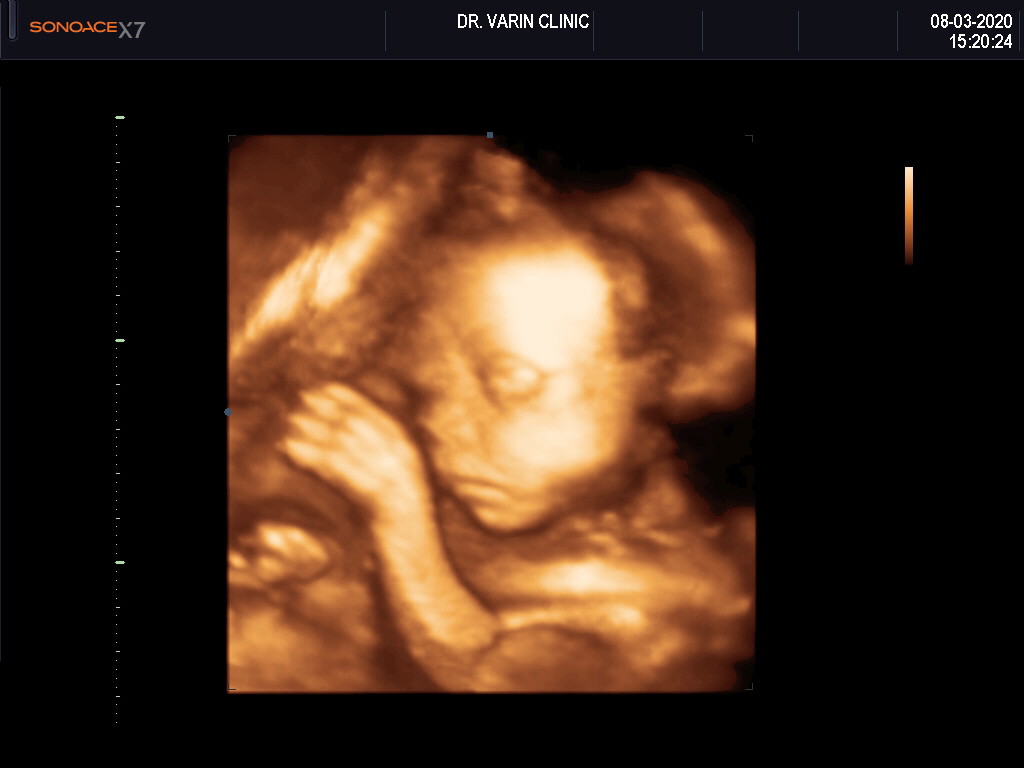

33w คะ